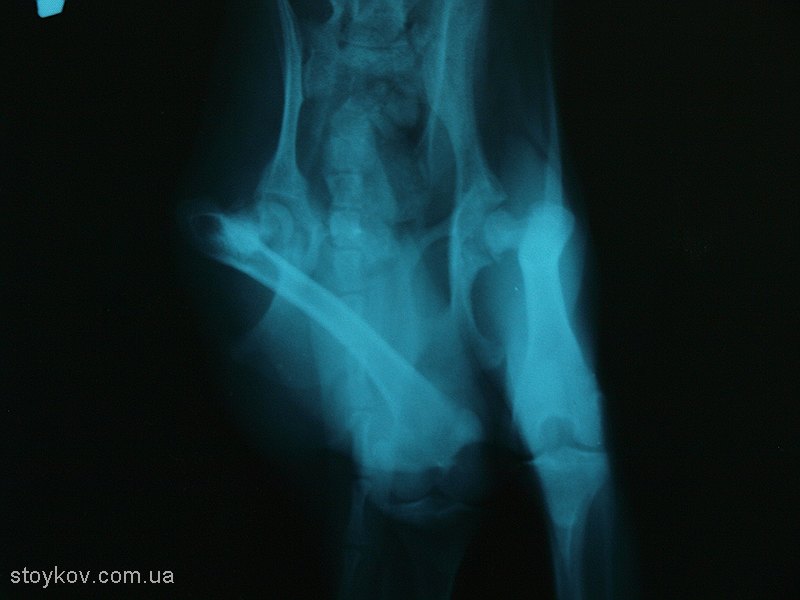

Рентгенологічна картина в перші місяці захворювання не відповідає реальному стану ураженого суглоба. (малюнок 2).

11 місяців той-терєр

Мал 2.

Цей факт добре підтверджує позицію відомого французького ортопеда Жана-Люка Шатре про те, що потрібно лікувати тварину а не рентгенівський знімок.